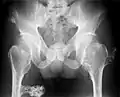

-

Multiple osteochondromas causing deformity of the forearm (shortening of the radius with secondary bowing of the ulna) -

Multiple osteochondromas at the pelvis -